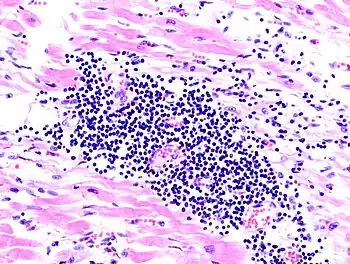

| A microscope image of myocarditis at autopsy in a person with acute onset of heart failure | |

The gold standard is the biopsy of the myocardium, in general done in the setting of angiography. A small tissue sample of the endocardium and myocardium is taken and investigated. The cause for the myocarditis can be only diagnosed by a biopsy. Endomyocardial biopsy samples are assessed for histopathology (how the tissue looks like under the microscope: myocardial interstitium may show abundant edema and inflammatory infiltrate, rich in lymphocytes and macrophages. Focal destruction of myocytes explains the myocardial pump failure.[11] In addition samples may be assessed with immunohistochemistry to determine which types of immune cells are involved in the reaction and how they are distributed. Furthermore, PCR and/or RT-PCR may be performed to identify particular viruses. Finally, further diagnostic methods like microRNA assays and gene-expression profile may be performed.